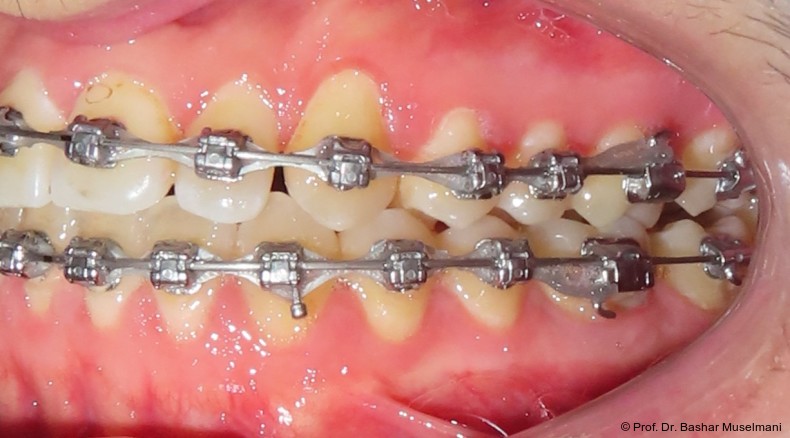

Die Abbildungen 1 bis 3 zeigen die initiale klinische und radiologische Ausgangssituation.

Zu Beginn der Nivellierungsphase wurden in beiden Kiefern 0.013" CuNiTi-Bögen eingesetzt (Abb. 4a–e).

Diese Sequenz ermöglichte eine schrittweise Ausformung der Zahnbögen, eine kontrollierte Torque-Expression sowie eine präzise Feineinstellung in der Abschlussphase (Abb. 5a–e).